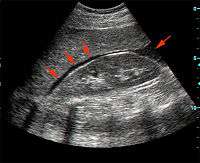

Focused assessment with sonography for trauma (commonly abbreviated as FAST) is a rapid bedside ultrasound examination performed by surgeons, emergency physicians and certain paramedics as a screening test for blood around the heart (pericardial effusion) or abdominal organs (hemoperitoneum) after trauma.[1]

The four classic areas that are examined for free fluid are the perihepatic space (also called Morison's pouch or the hepatorenal recess), perisplenic space, pericardium, and the pelvis. With this technique it is possible to identify the presence of intraperitoneal or pericardial free fluid. In the context of traumatic injury, this fluid will usually be due to bleeding.

FAST is most useful in trauma patients who are hemodynamically unstable. A positive FAST result is defined as the appearance of a dark ("anechoic") strip in the dependent areas of the peritoneum. In the right upper quadrant this typically appears in Morison's Pouch (between the liver and kidney). This location is most useful as it is the place where fluid will collect with a supine patient. In the left upper quadrant, blood may collect anywhere around the spleen (perisplenic space). In the pelvis, blood generally pools behind the bladder (in the rectovesicular space). A positive result suggests hemoperitoneum; often CT scan will be performed if the patient is stable[13] or a laparotomy if unstable. In those with a negative FAST result, a search for extra-abdominal sources of bleeding may still need to be performed.[13] Rip's absent organ sign has been described as suggestive for diaphragmatic rupture.[14]